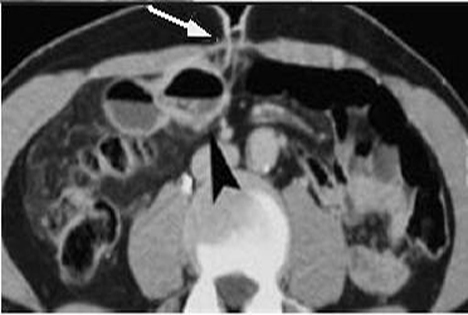

Divereticulite de

Meckel severe correspondant a une perforation

bouchee de la diverticule : Image infiltration de

graisse peri diverticulaire et la presence de gaze

extra digestif par la perforation bouche a temoin (

fleche blanche ) . |